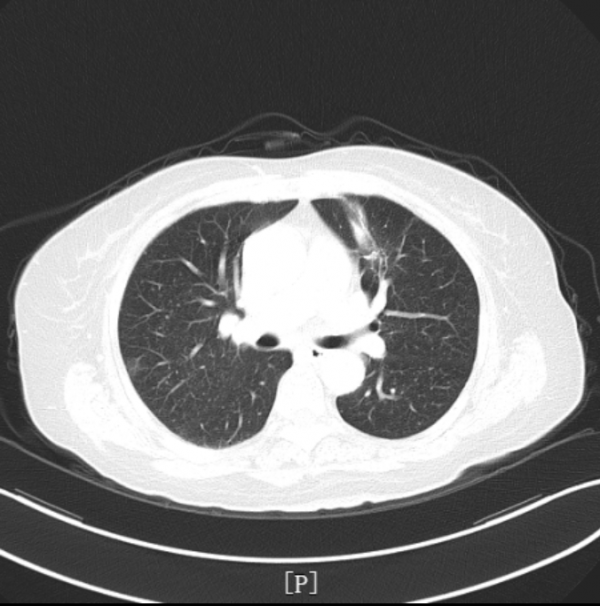

▎入院影像學檢查:

- 肺部CT檢查提示:左肺上葉前段佔位性病變,伴遠端阻塞性炎症及肺不張,考慮:周圍型肺癌可能性大。

治療後安排患者複查肺部CT,提示左肺腫瘤性病變較前明顯縮小。療效評估PR。

該患者2021年5月因“咳嗽咳痰伴發熱10余天”入院,完善肺部CT檢查提示:左肺上葉前段佔位性病變,伴遠端阻塞性炎症及肺不張,考慮:周圍型肺癌可能性大。頭部MRI檢查提示:雙側小腦半球點狀異常強化灶,考慮轉移瘤病灶。雙側大腦半球及小腦半球腦溝鑄型明顯異常強化,考慮肺癌軟腦膜轉移。腦膜轉移較腦實質腫瘤轉移少見,但肺癌腦膜轉移患者預後更差。患者在2021年6月進行支氣管鏡檢查,取腫瘤組織病理檢查也證實,其左肺上葉佔位系肺腺癌。入院診斷:左肺上葉肺腺癌伴腦轉移。分級:T2NxM1c IV期。

根據《CSCO 2021非小細胞肺癌診療指南》推薦,治療組給予患者培美曲塞二鈉化療+貝伐珠單抗全身治療。直至患者完成三個週期聯合治療後,複查胸部CT提示:左肺上葉腫瘤病灶較前明顯縮小。且治療期間不良反應經對症治療後迅速緩解,患者耐受性良好。